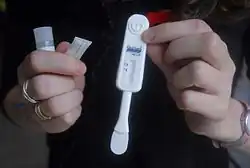

Most saliva testing is performed using enzyme-linked immunosorbent assay (ELISA), polymerase chain reaction (PCR), high-resolution mass spectrometry (HRMS), or any number of newer technologies such as fiber-optic-based detection. All of these methods enable detection of specific molecules like cortisol, C-reactive protein (CRP), or secretory IgA. This type of testing typically involves collection of a small amount of saliva into a sterile tube followed by processing at a remote laboratory. Some methods of testing involve collecting saliva using an absorbent pad, applying a chemical solution, and monitoring for color change to indicate a positive or negative result. This method is commonly used as a point-of-care (POC) technique to screen for HIV. However, using absorbent pads and chemical solutions could very easily skew the results of immunoassays. Research by Dr. Douglas A. Granger and colleagues shows that outcomes for testosterone, DHEA, progesterone, and estradiol biomarkers are elevated when cotton-based collection materials are used as opposed to samples collected by other methods (i.e. passive drool).[10] Researchers are currently examining the expanding role of saliva testing as part of routine dental or medical office examinations where saliva collection is simple to perform.[9]

The accuracy of saliva anti-HIV antibody testing has been demonstrated in numerous studies; two recent large-scale studies found both sensitivity and specificity to be 100%. The first of these was published in 2008 by Zelin, et al., and compared saliva antibody testing and serum antibody testing using ELISA technique in 820 individuals.[53] The second study, conducted by Pascoe, et al., compared saliva antibody testing to serum antibody testing using ELISA followed by confirmatory Western Blot analysis in 591 individuals.[54] The accuracy of saliva anti-HIV antibody testing has been confirmed by many additional studies, leading to approval of this method by the U.S. Food & Drug Administration in 2004.[55]